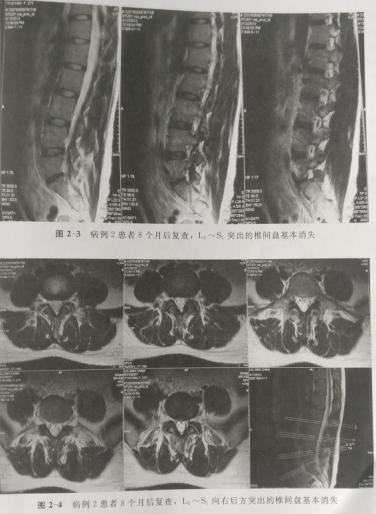

病例2.刘某,女,28岁,于2011年8月25日确诊为腰椎间盘突出症,磁共振显示L5--S1椎间盘向右后方突出,达1区级右2区、B域(椎管矢状径的1/2),硬膜囊明显受压,右侧S1神经根受压。因无明显根性体征,行保守治疗并随访,体征完全消失。8个月后复查磁共振突出髓核基本消失消失。

下面将某疼痛学杂志的报道及图片展示如下;